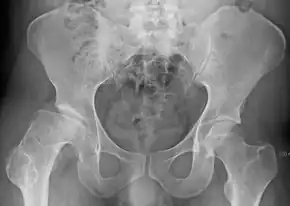

Radiograph of a person with Legg–Calvé–Perthes disease

X-rays of the hip may suggest or verify the diagnosis. X-rays usually demonstrate a flattened, and later fragmented femoral head. A bone scan or MRI may be useful in making the diagnosis in those cases where X-rays are inconclusive. Usually, plain radiographic changes are delayed six weeks or more from the clinical onset, so bone scintigraphy and MRI are done for early diagnosis. MRI results are more accurate, i.e., 97 to 99% against 88 to 93% in plain radiography. If MRI or bone scans are necessary, a positive diagnosis relies upon patchy areas of vascularity to the capital femoral epiphysis (the developing femoral head).